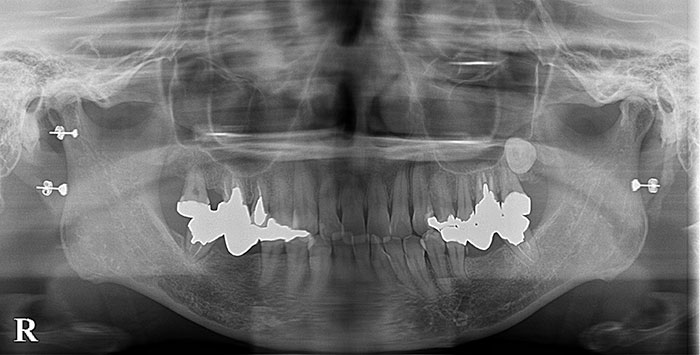

歯の移植の症例

Before

After

親知らずの歯を移植したケースです。患者様はとても喜ばれておりました。